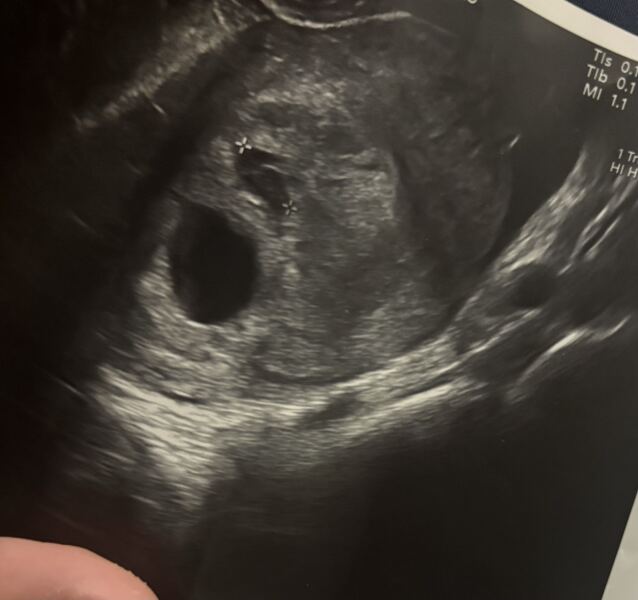

I had another scan yesterday just to check everything. They could still see baby with a little flicker, measuring 5+5, but they also saw another ‘sac’ above it. The sonographer said this could either be a small bleed that should resolve on its own (she confirmed it wasn’t a subchorionic haematoma), or it could be another pregnancy. However, she felt it “didn’t look promising” as it appeared empty.

She didn’t spend much time on the second sac, just measured the diameter. On the still scan it looks smaller than the viable pregnancy, but when she moved the probe they actually looked quite similar in size… empty sac measured 1.11cm and the viable pregnancy was 1.36cm. I thought I saw something in it, but obviously I’m not qualified so trusting what she said.

She’s asked me to come back in 2 weeks as she couldn’t be 100% certain, although she did seem fairly confident it wasn’t another pregnancy.

For any twin mums (or anyone who’s had something similar) – does this sound or look familiar at all? Trying not to Google myself into madness as my partners dad is a twin and they also run in my side of the family 🙈 I’ve had no symptoms at all really, maybe the odd wave of nausea!